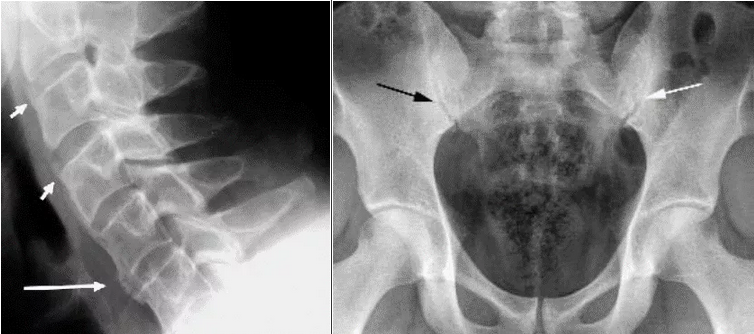

Спондилит - воспаление структур осевого скелета. Проявляется воспалительной болью в спине (ВБС), которая оценивается по критериям ASAS (2009).

Сакроилиит характеризуется воспалительной болью в нижней части спины и/или перемежающейся болью в ягодицах. Боль может иррадиировать по задней поверхности бедра, быть кратковременной, по типу "прострела" и "радикулита".

Аксиальное поражение при ПсА имеет ряд особенностей. В 25% случаев сакроилиит и спондилит при ПсА протекают латентно (без боли). Сакроилиит при ПсА, в отличие от АС, – часто асимметричный. Для ПсА характерно медленное рентгенологическое прогрессирование сакроилиита, полный анкилоз КПС на фоне длительного течения заболевания отмечается значительно реже, чем при АС (до 6% пациентов). При ПсА возможно поражение позвоночника (рентгенологические признаки спондилита) без сакроилиита, чего не наблюдается при анкилозирующем спондилите (АС). При ПсА, в противоположность АС, синдесмофиты чаще малочисленны, расположены асимметрично, в случайном порядке, не вдоль ≪последовательно идущих≫ позвонков, имеют больший размер и объемную форму, встречаются паравертебральные синдесмофиты (ПВС) – особый вариант обызвествления передней продольной связки позвоночника. ПВС представляют собой широкие грубые оссификаты, которые отстоят от края тела позвонка. Также наблюдаются краевые синдесмофиты (КС) – вертебральные оссификаты, отходящие от края тела позвонка вверх. КС могут образовывать ≪мостики≫ между позвонками. КС и ПВС ориентированы вверх (сужения смежного межпозвонкового промежутка не наблюдается). Это отличает их от выявляемых при дегенеративных заболеваниях позвоночника остеофитов (или спондилофитов), которые ориентированы горизонтально, около измененного диска (сужение межпозвонкового промежутка). Нередко, несмотря на существенные рентгенологические изменения, у больных отсутствуют заметные функциональные нарушения, что также отличает спондилит при ПсА от поражения позвоночника при АС. Спондилит и сакроилиит могут наблюдаться при любой клинической форме ПсА.

Рисунок 10. Слева: Рентгенограмма шейного отдела позвоночника в боковой проекции. Псориатический спондилит. Синдесмофиты (короткие стрелки) и обызвествление (длинная стрелка) передней продольной связки в шейном отделе. Справа: Рентгенограмма таза. Двусторонний асимметричный сакроилиит III стадии слева и I стадии справа (черная стрелка). Видны широкая зона остеосклероза (>3 мм), сужение и неровность щели КПС, частичный анкилоз (белая стрелка). Сакроилиит считается асимметричным, когда между правым и левым КПС различия больше, чем на одну стадию.